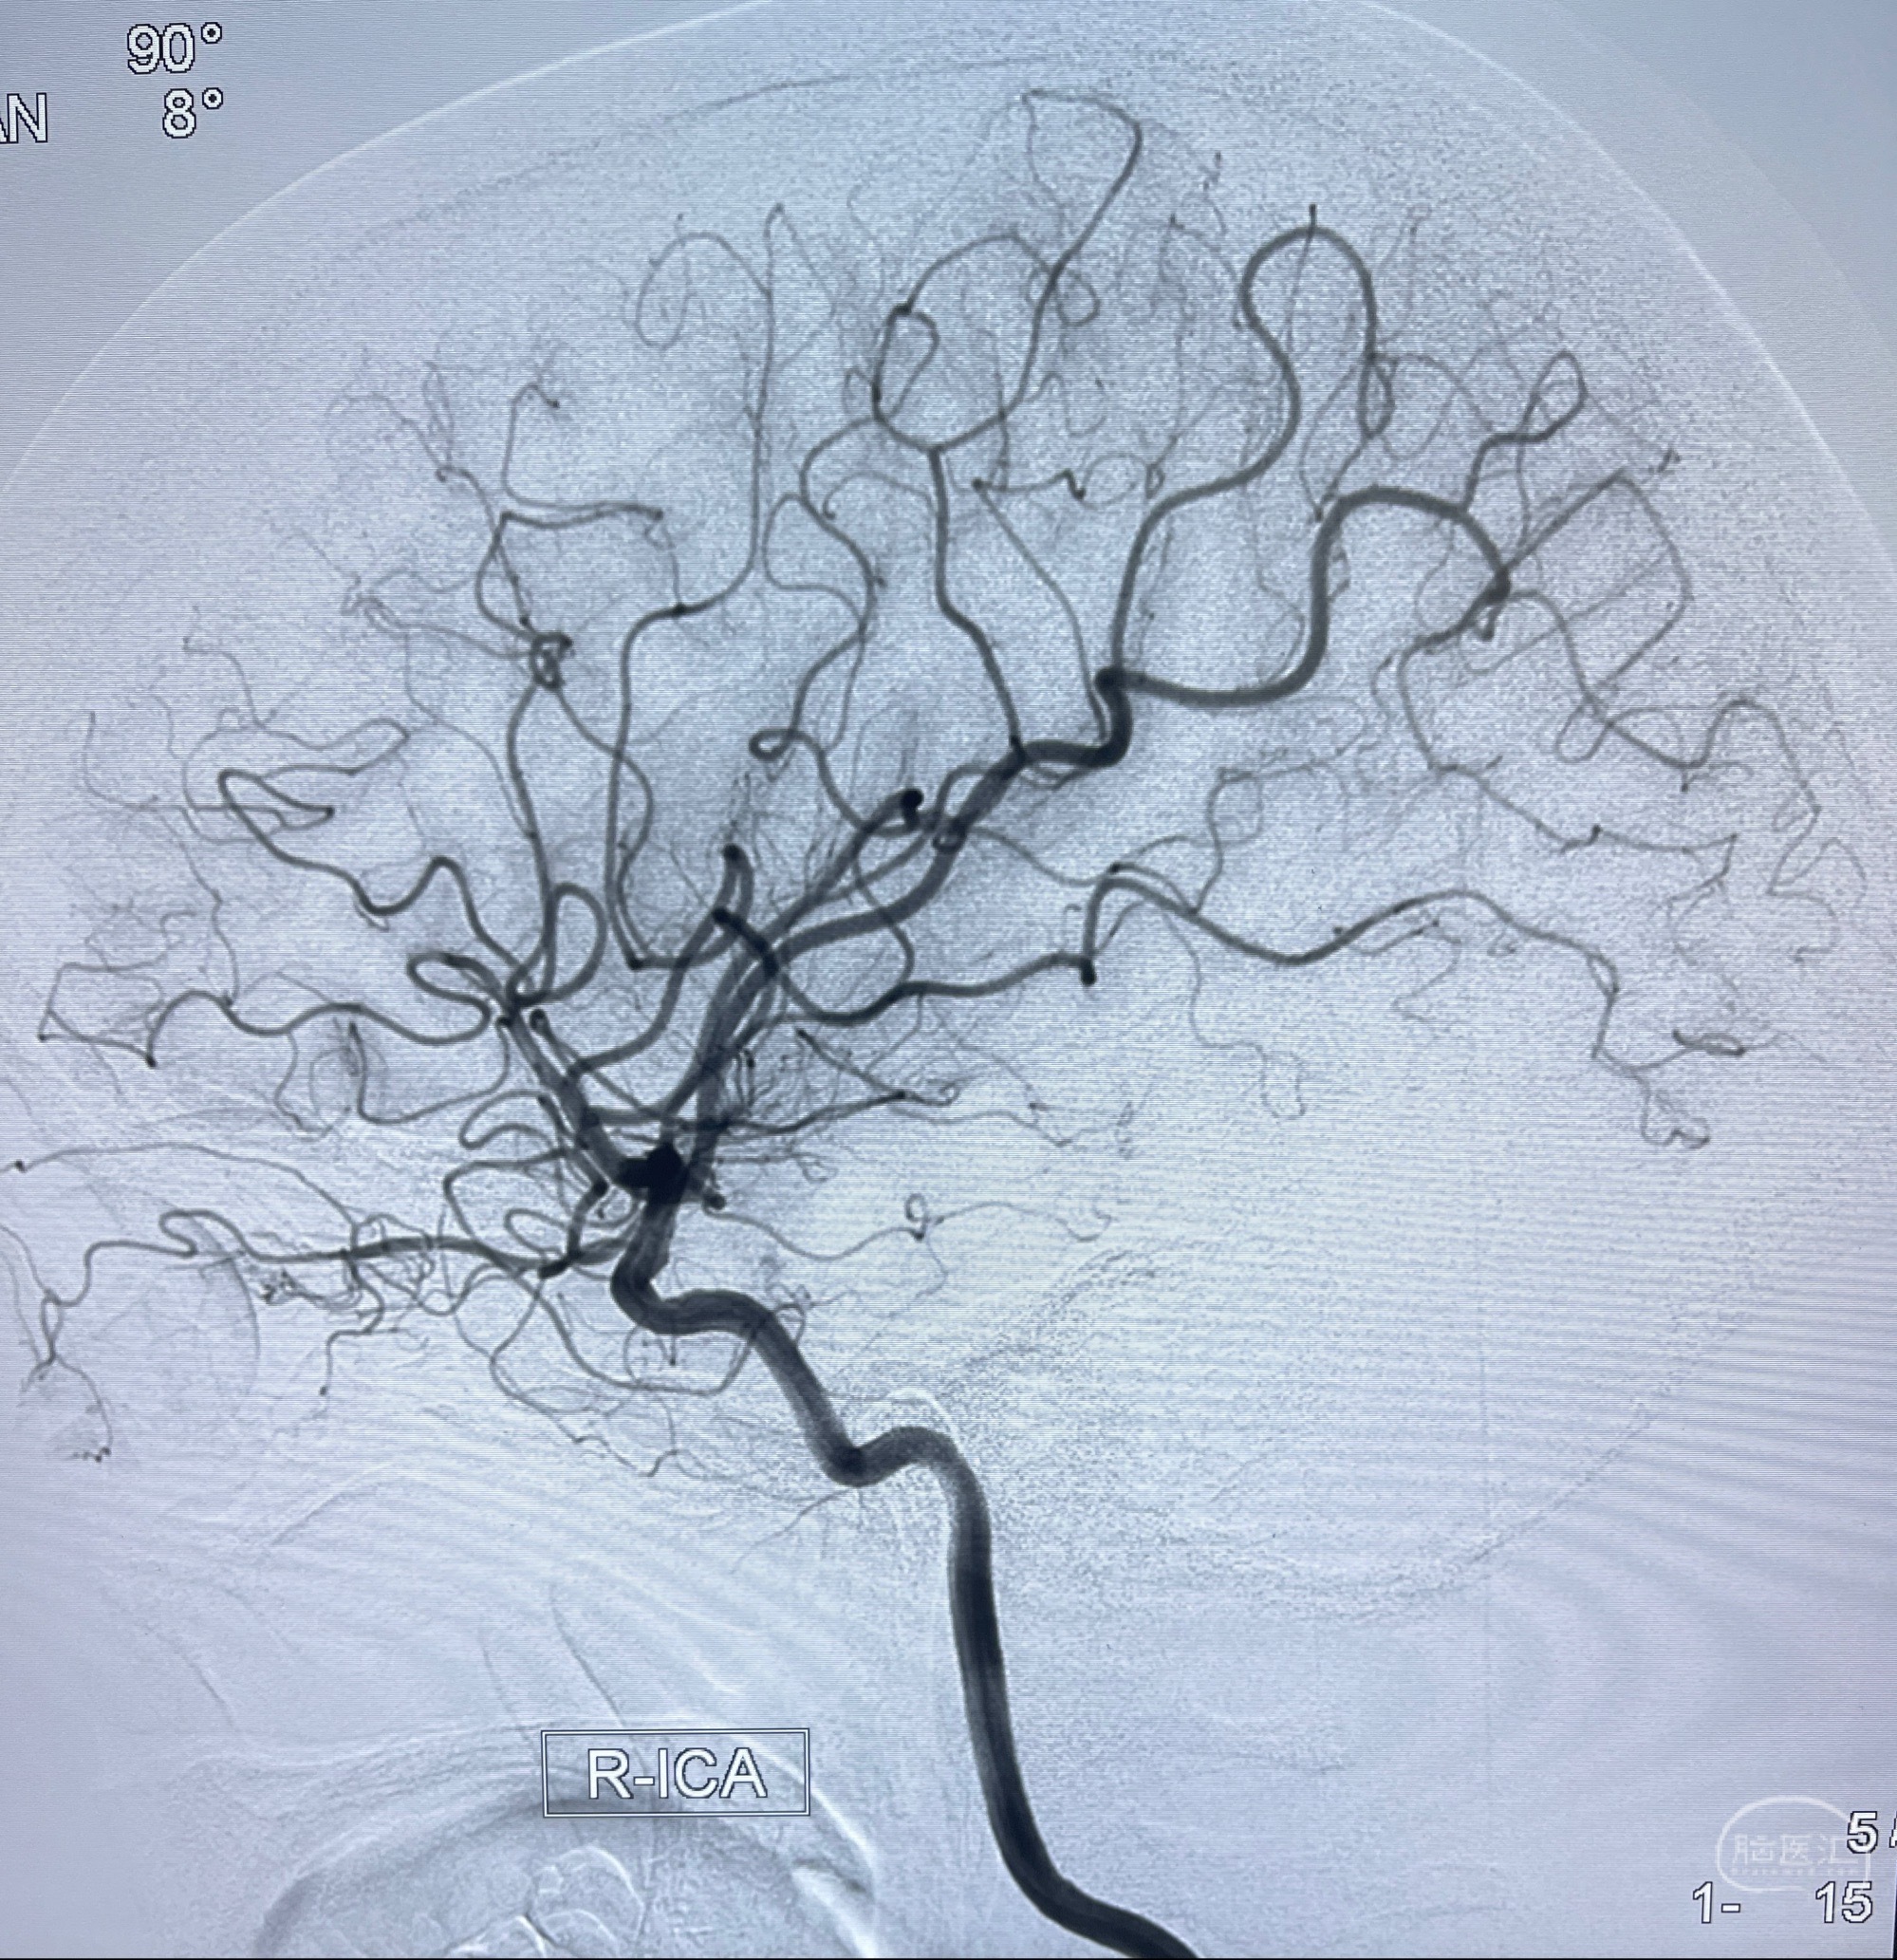

2023-08-14DSA:

左侧大脑中动脉动脉瘤,约2.6-2.8-3.4-2mm大小(瘤颈部、瘤体部、瘤高)

1.左侧大脑中动脉动脉瘤,约2.6-2.8-3.4-2mm大小(瘤颈部、瘤体部、瘤高)

2.外科手术夹闭or介入支架辅助栓塞